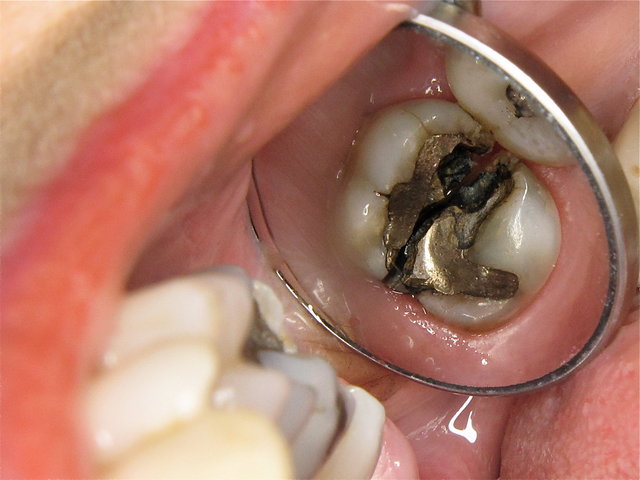

Alte undichte Amalgam-Füllungen mit Karies und Rissen ...

Composit-Füllungen by CLINICDENT ✓